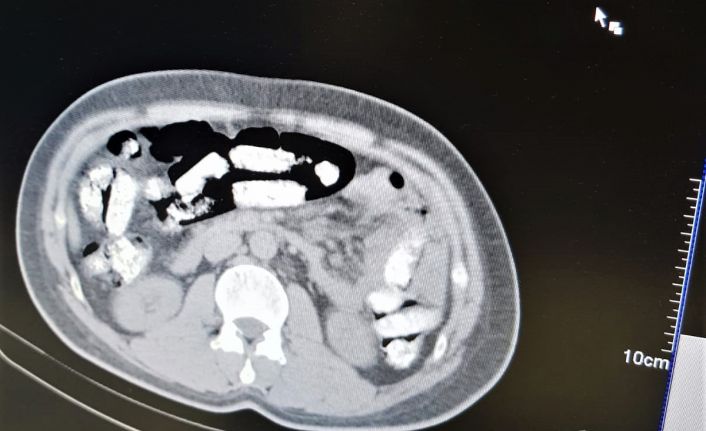

Erzincan İl Emniyet Müdürlüğü Narkotik Suçlarla Mücadele Şube Müdürlüğü ekiplerince uyuşturucu madde kuryeliği yapan şahıslara yönelik İran otobüsleri üzerinde yapılan uygulamada; İran otobüsünde yolculuk yapan Abdulmennan S. isimli İran uyruklu kişinin yutma yöntemiyle uyuşturucu taşıdığı değerlendirilmesi üzerine, Erzincan Mengücek Gazi Eğitim ve Araştırma Hastanesinde zanlının bedeninden 106 fişek halinde toplamda 1 kilo 198 gram Afyon Sakızı ele geçirildi. Abdulmennan S. hakkında TCK 188 suçundan yapılan tahkikat sonrası sevk edildiği mahkemece tutuklanarak cezaevine teslim gönderildi.